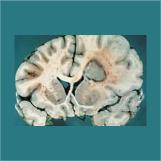

Dr. Zlokovic's research links intravascular Alzheimer's amyloid-β (Aβ) to Aβ deposition in brain, transport across the blood-brain barrier (BBB) and neuroinflammation as a primary mechanism in Alzheimer's disease pathogenesis. Faulty clearance due to dysregulated transport of Aβ is shown to potentiate neuroinflammation and cerebral β-amyloidosis associated with reduced cerebral blood flow (CBF), triggering "silent strokes" in models of Alzheimer's disease. From the therapeutic prospective, his investigations show that new peripheral Aβ binding agents protect brain from Aβ/amyloid accumulation, neuroinflammation and suppression of CBF. In addition, his work on activated protein C (APC) in the CNS demonstrates that APC prevents leukocyte trafficking across the BBB and protects brain from injury and/or apoptosis.